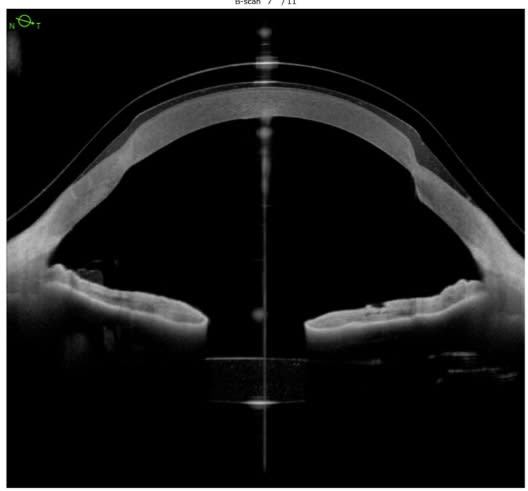

Investigators evaluate how iris pigmentation influences Scheimpflug-derived corneal densitometry measurements.

A recent study found that individuals with light-colored irises exhibited a 6.6% relative increase in corneal densitometry compared to those with dark-colored irises. The observational study involved 91 eyes from 47 healthy White participants aged 21 to 41, all with normal vision and no ocular history. Using Scheimpflug imaging, the researchers assessed corneal density and found that lighter irises correlated with higher densitometry values. Despite valuable findings, the narrow age range and controlled conditions may limit the generalizability of results.